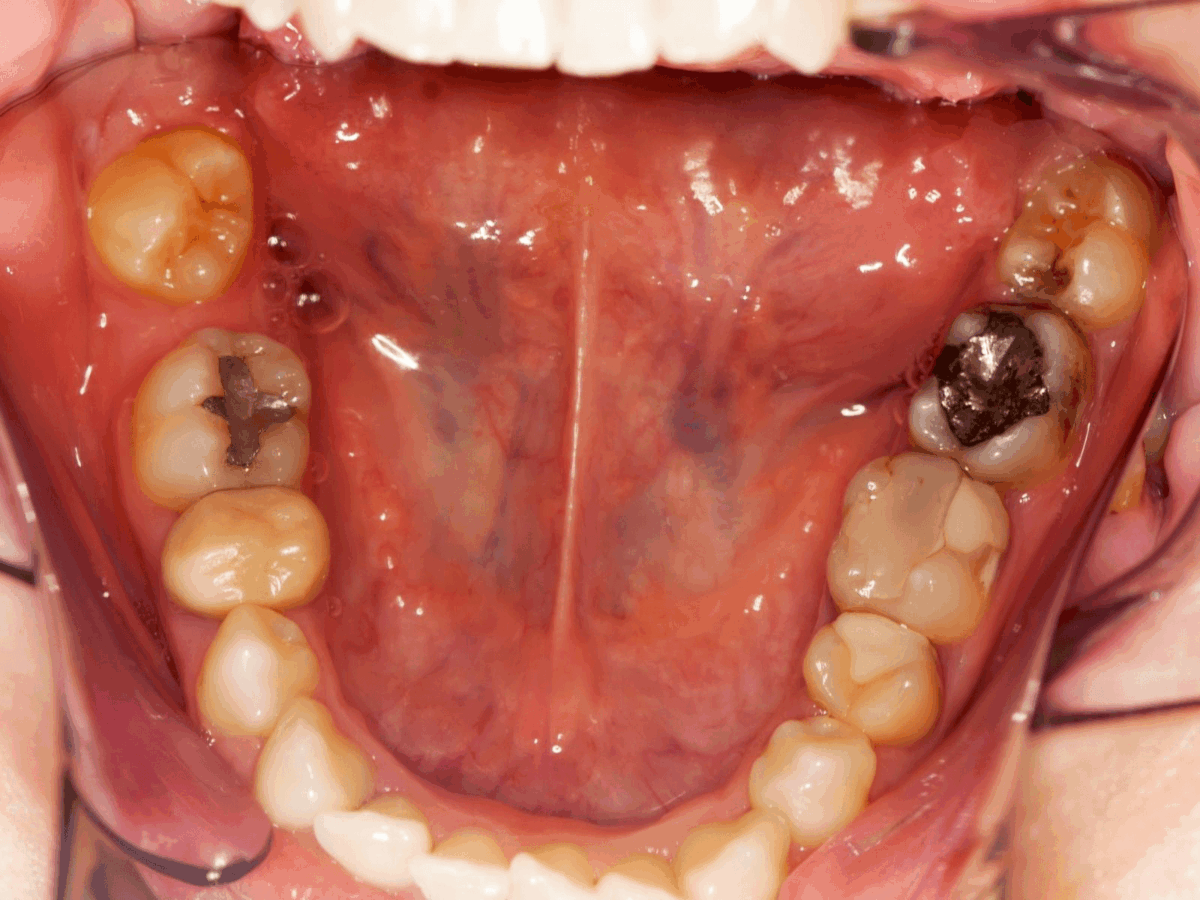

Amalgam fillings have been used in dentistry for many decades. They are strong and can be used every day. Because of this, they are often placed in the back teeth.

The darker colour makes them less noticeable in molars. When people explore types of dental fillings, amalgam often appears as a functional option. Longevity is usually the main advantage discussed.